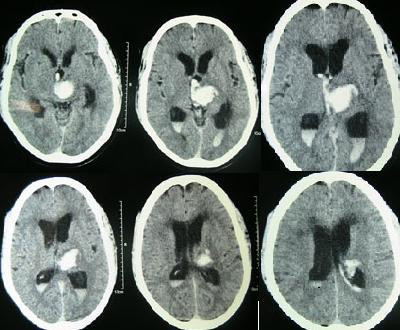

هل يساعد التداخل الجراحي الطفيف التوغل في علاج النزف الدماغي فوق الخيمة؟ |

للإجابة عن هذا السؤال وزّع الباحثون في 32 مركزًا طبيًا 264 مريضًا على مجموعتين، الأولى (154 مريضًا) تلقت العلاج الطبيّ فقط، بينما أُجري تدخل جراحي طفيف التوغل لمرضى المجموعة الثانيّة (82 مريضًا).تراوح عمر المرضى بين الثامنة عشرة والثمانين، بينما شغل النزف الدماغي حيزًا بين 20 إلى 80 مل. وحصل المرضى على ست نقاط أو أعلى في مقياس NIHSS، بينما توزعت نتائج مقياس جلاسغو للغيبوبة بين 5 و15. |

حقوق الصورة: ويكيمديا |

شمل الهدف الأولي للدراسة الموت والإعاقة بعد 180 يومًا من العلاج اعتمادًا على مقياس mRS، بينما كان الهدف السلامة الأولي معدل الوفيات خلال 30 يومًا. |

ووصلت الدراسة إلى أنّ التداخل الجراحي طفيف التوغل لم يساهم في تخفيض معدل الوفيّات خلال أول 30 يوم ولم يحسن من نسبة الإعاقة خلال 180 يومًا في مرضى النزيف الدماغي فوق الخيمة مقارنةً بالعلاج الطبي المعتمد. |

نُشرت الدراسة في دورية جاما. |